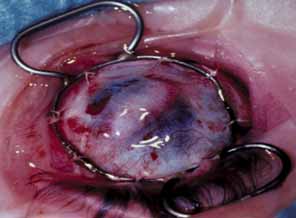

Lens involvement can include corneolenticular adhesion, corneolenticular contact, or cataract. In cases in which the lens is involved, vitreoretinal and systemic abnormalities occur more frequently.117,118 Various interactions between the cornea and lens include a clear, partially dislocated lens firmly adhering to the cornea after moving back and forth.116 The lens may initially lie against the posterior cornea and later spontaneously move into the posterior chamber.120 A small stalk may connect the lens to the cornea (Fig. 21).121 An hourglass-shaped lens may occupy the pupil or a shrunken lens may adhere firmly to the posterior cornea. These findings emphasize the importance of examination with ultrasound if the opacity is too dense, blocking a clear view of the posterior structures. Histopathologically, the lens capsule is usually intact; however, direct contact between the corneal stroma and the lens cortex sometimes can occur (Fig. 22).

Fig. 21 Surgical treatment of congenital corneolenticular adhesion. A. Knife needle separates lens stalk from overlying corneal opacity. Note anterior chamber irrigation tube. B. Corneolenticular adhesion, keratoiridial adhesions, and knife needle separating lens from cornea. C. Slit lamp photograph taken 8 years after original surgery shows healed posterior corneal defect with slight scarring. (Waring GO, Parks MM: Successful lens removal in congenital corneolenticular adhesion (Peters anomaly). Am J Ophthalmol 83:526, 1977)